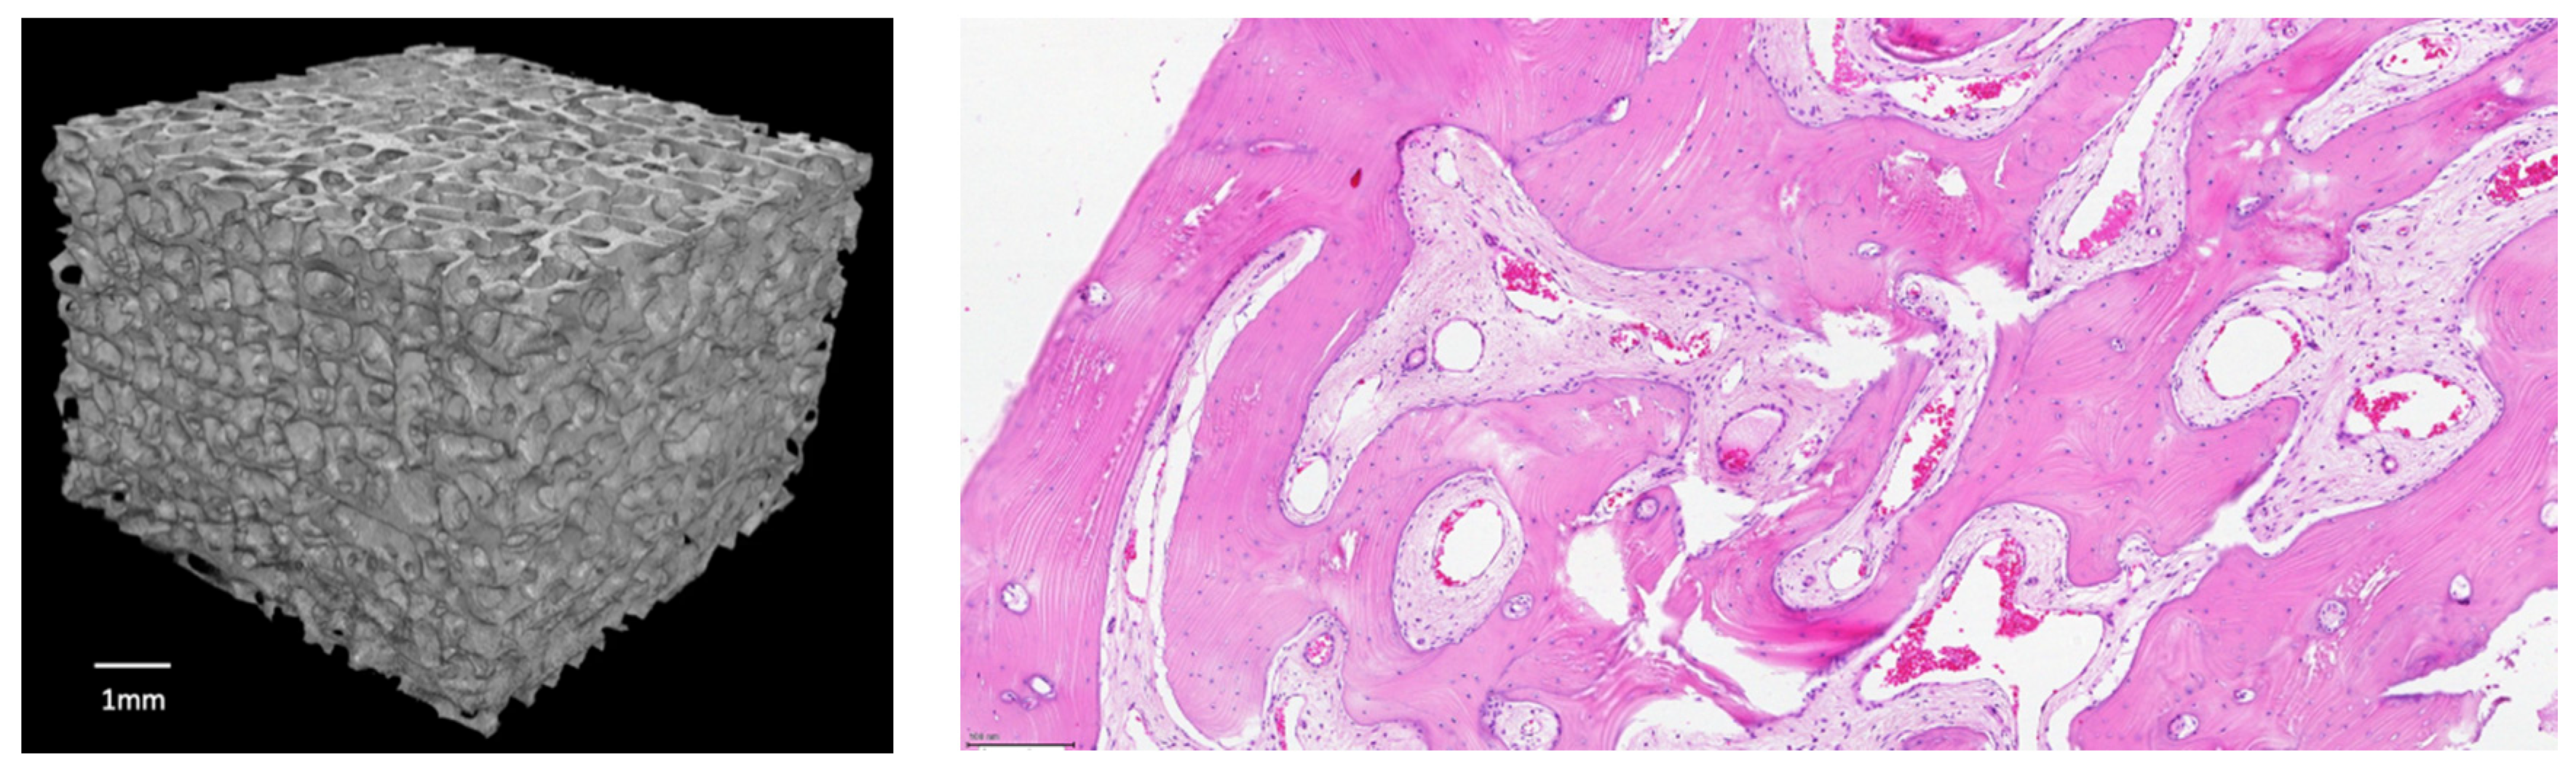

Bovine xenografts are valid scaffolds for bone grafting as they mark scores which are very close to human cancellous bone, even if the sterilization process may alter their biomechanical properties [16]. Recently, a low temperature processing of the bone and the addition of composite technology to the xenograft to increase its biological and mechanical performances has been scoring promising results in clinical practice [17,18,19]. SmartBone® (SB) (IndustrieBiomedicheInsubri IBI SA; Mezzovico-Vira, Switzerland) is a composite xeno-hybrid graft that is obtained from a low-temperature processed bovine-derived mineral matrix extracted from the adult bull internal part of femur heads, enriched with the synthetic aliphatic polyester poly(L-lactide-co-ε-caprolactone) (PLCL) and Arg-Gly-Asp (RGD)-containing collagen fragments (obtained from animal-derived gelatin), which altogether improve elasticity, blood affinity and cell attachment, while also providing an open porous and interconnected microenvironment (av. pore size is 250 microns) favorable to cell and vessel colonization, and finally allowing a complete remodeling overtime [18,19,20]. The aminoacidic RGD sequence, alias the tripeptide Arg-Gly-Asp consisting of Arginine, Glycine, and Aspartate, is indeed the preferred motif with the highest affinity for cellular integrins. SB mechanical performances can be compared with human healthy cortico-cancellous bone and are summarized in Table 1 (adapted from [20]). Furthermore, a reconstruction from a CT scan on an SB block and a histologic sample taken after SB implantation can be found in Figure 1.

Figure 1. (left) 3D reconstruction from a CT scan (Bruker system) on an exemplificative SB block 7 × 7 × 7 mm (reference bar is 1 mm); (right) H/E staining on a histologic sample taken after 2.5 years post SB implantation: the graft is completely substituted, and the osteogenesis has formed a lamellar bone with cement lines; a lot of osteocytes inside the lacunae and a good angiogenesis are evidenced (adapted from Grecchi et al. [21]).